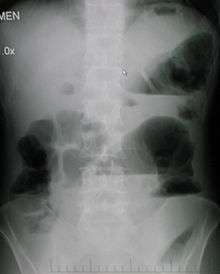

Upright abdominal X-ray demonstrating a small bowel obstruction. Note multiple air fluid levels. | |

Radiological signs of bowel obstruction include bowel distension and the presence of multiple (more than six) gas-fluid levels on supine and erect abdominal radiographs.